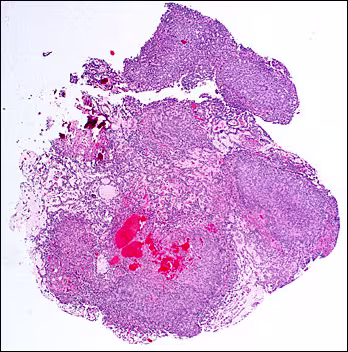

The tissue sections showed an epithelial proliferation exhibiting a variable microscopic pattern. At low power, the lesion showed solid, nodular masses of basophilic cells intermixed with less cellular areas (Figures 2 and 3).

Figure 2. Low-power scanning photomicrograph of one portion of the lesion showing nodular groups of basophilic cells (Hematoxylin and eosin stain).